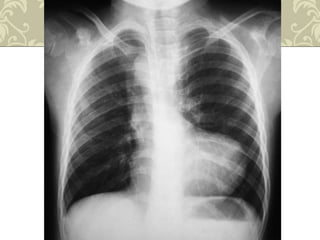

Radiografia de tórax

 Coração em forma de bota( couer em sabot);

 Circulação pulmonar diminuída;

 Arco aórtico do lado direito(25%);

 Aorta ascendente é proeminente.